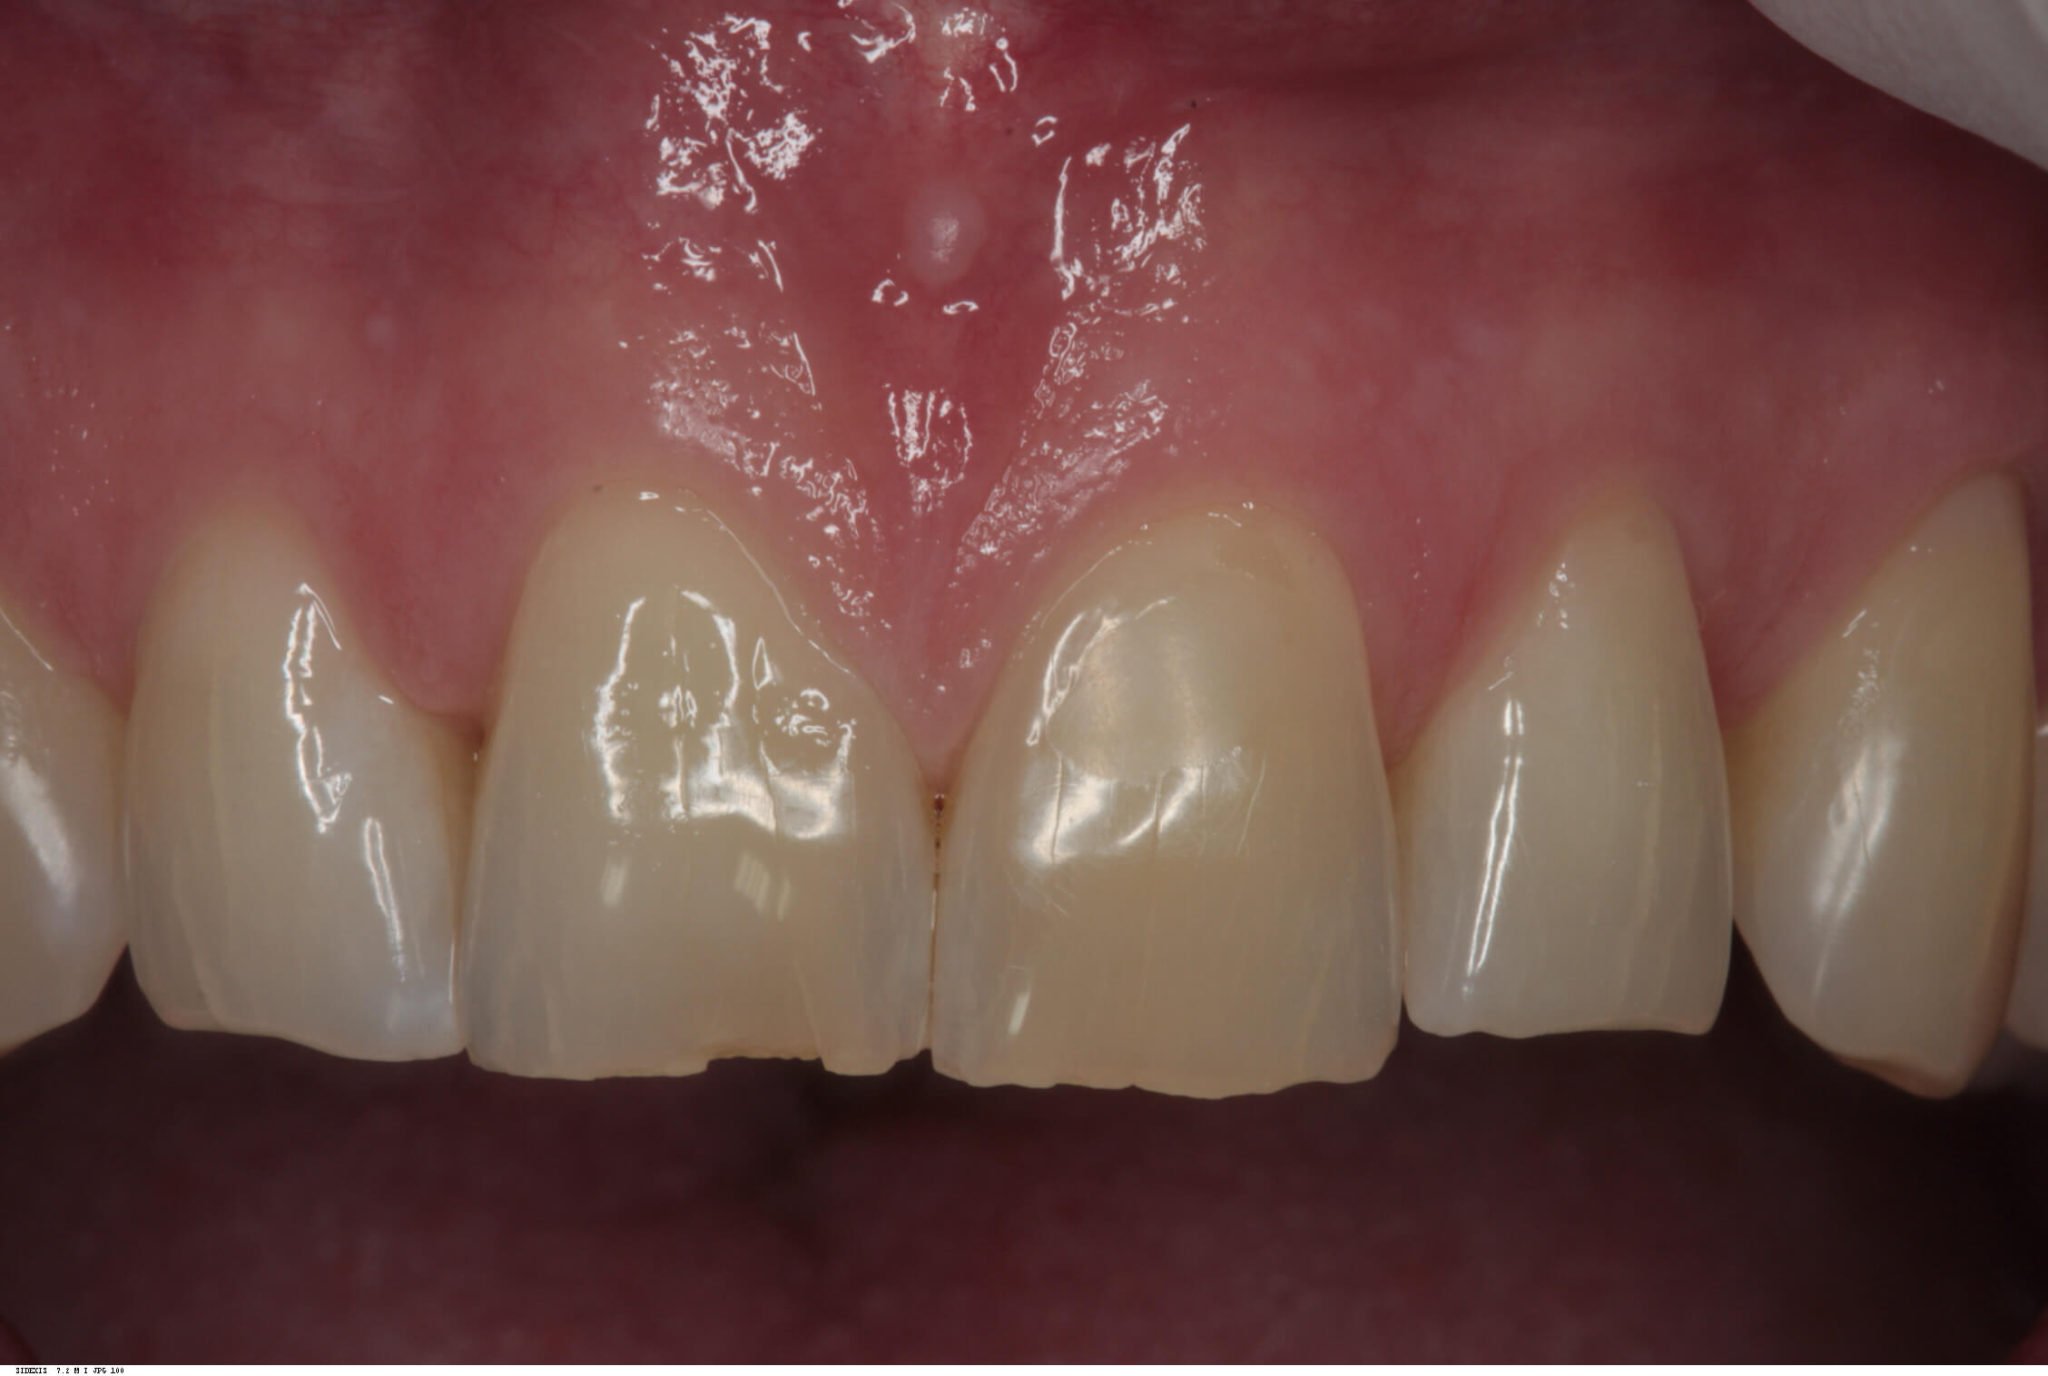

Following a four month post-operative review and confirmation of integration, this implant was then restored with a screw retained integrated abutment / veneered zirconia crown. The crown was then inserted and abutment screw torqued to 35 Ncm. The access cavity was restored with PTFe tape and composite resin. The occlusion was adjusted to ensure light Shim stock hold in ICP, and smooth concave protrusive guidance shared with the neighbouring central incisor.

Review

Reviews carried out at both one year and then six years post operative, showed stable gingival symmetry, and the radiographs showed excellent bone level maintenance.